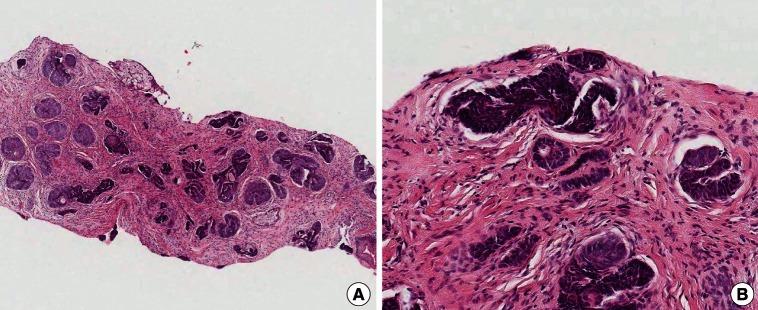

Basal cell carcinoma presenting as a hypertrophic scar.

Arch Plast Surg. 2013 May;40(3):289-91. doi: 10.5999/aps.2013.40.3.289. Epub 2013 May 16.

https://cdn.ncbi.nlm.nih.gov/pmc/blobs/3f2b/3665885/5eb40a70b375/aps-40-289-g002.jpg